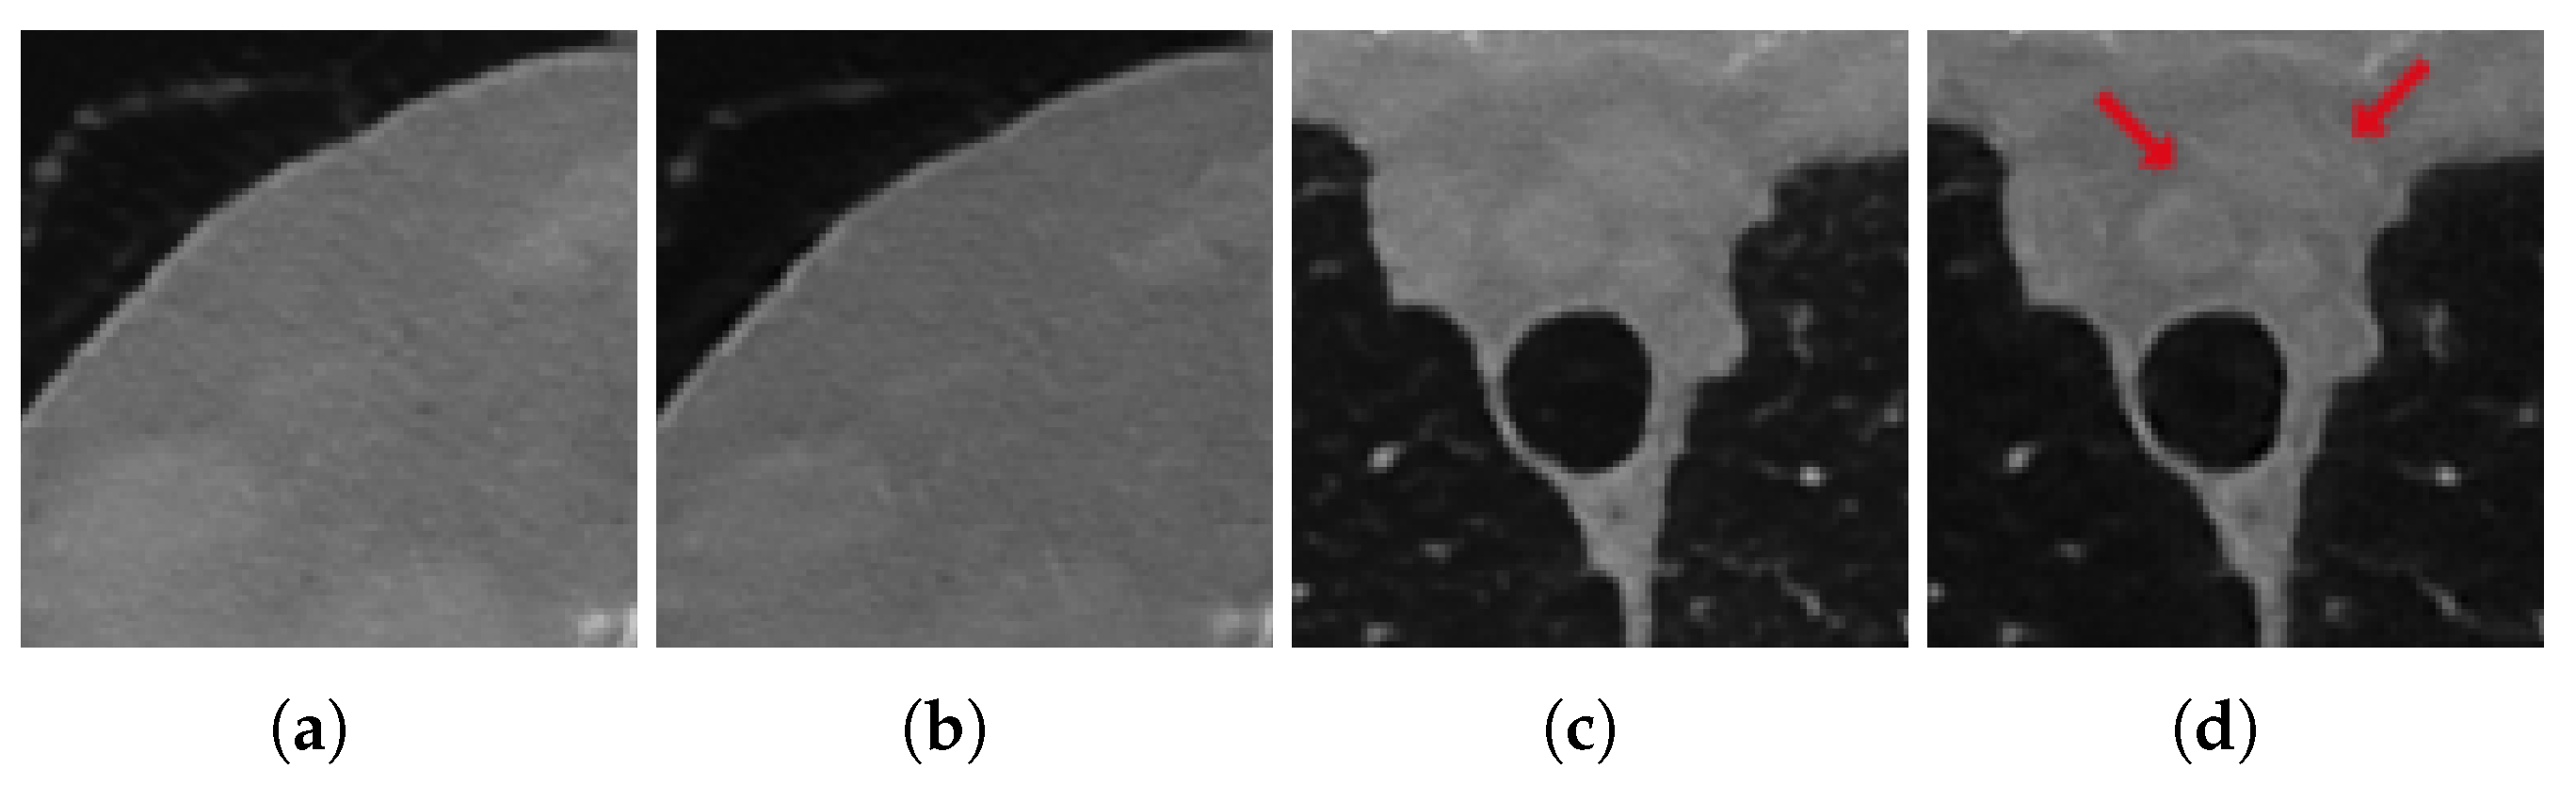

| RE | PSNR | SSIM | FSIM | |

|---|---|---|---|---|

| FBP | 0.9932 | 86.45 (33.90) | 0.2962 | 0.6819 |

| ResUNet | 0.1016 | 106.38 (41.71) | 0.9324 | 0.9478 |

| 3L-SSNet | 0.1309 | 104.34 (40.91) | 0.9021 | 0.9474 |